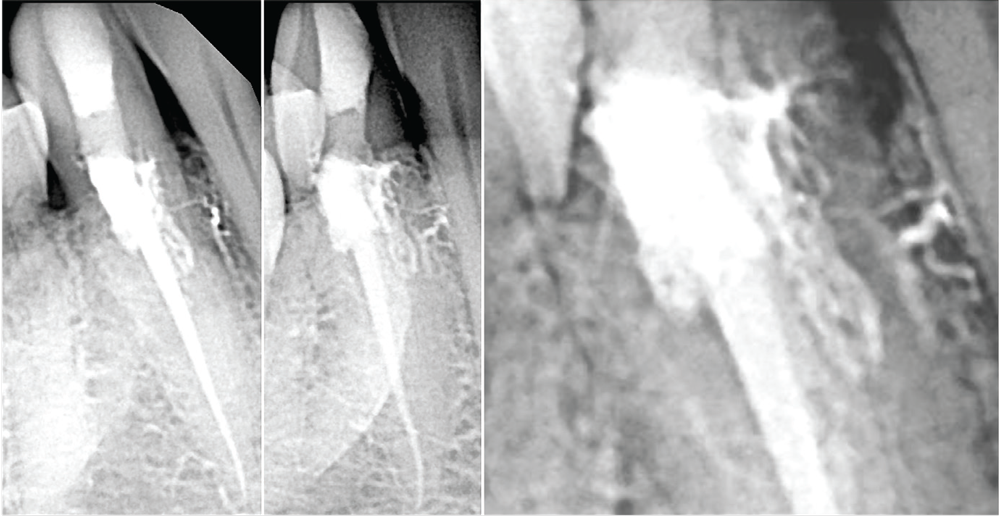

Figs. 6a and 6b: Mandibular molar with severe, multiplanar curvatures of all canals. The D canal was instrumented with a single 3D Shaper; the mesial canals were shaped with a 15-.06 Edge rotary file. All the canals were filled with BC HiFlow Sealer and EdgeCore gutta percha carriers (Edge Endo).

Carrier-based obturation also works well paired with bioceramic sealer. Three millimeters of sealer is syringed into each canal, an XP-Finisher (Brasseler) is used to spread a thin coat of sealer on canal walls, then the oven-heated obturator is placed 1mm short of full length. With improved heat resistance, carrier placement with bioceramic sealer is now identical to placement of carriers with traditional sealers, except patients have little or no postoperative discomfort because of the complete biocompatibility (Figs. 6a and 6b).